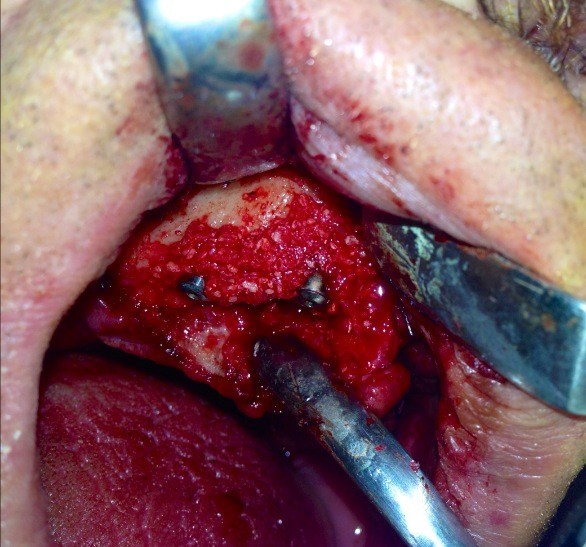

Impianti post-estrattivi complessi con innesto osseo

Impianti Post-estrattivi con innesto di osso e tessuto epitelio-connettivale